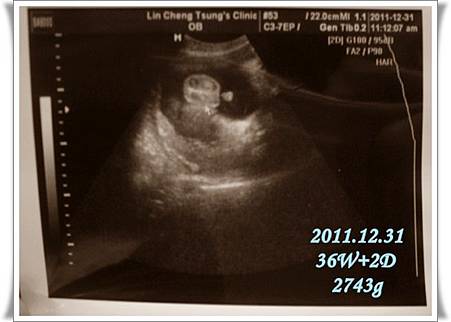

倒數的最後一個月

每個星期都得去做例行性產檢

索性累積四次再PO一篇文

記錄一下二寶的健康狀況…